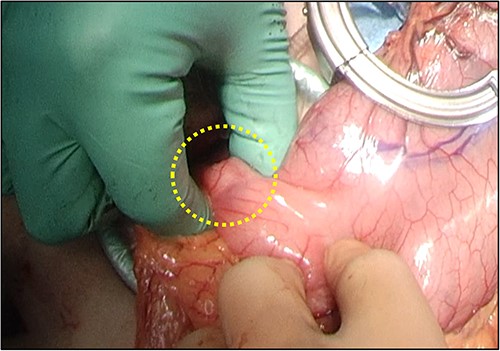

Overall, the esophageal stricture was determined to be benign and resistant to endoscopic treatment; thus, surgical resection of the esophagus was scheduled. She underwent thoraco-laparoscopic subtotal esophagectomy, followed by gastric tube reconstruction via the posterior sternal route. During mini-laparotomy to prepare the gastric tube, partial duodenectomy was performed for excisional biopsy of the duodenal mass (Fig. 4). Postoperatively, the patient had no morbidities.

Partial duodenectomy was performed to resect the duodenal mass during mini-laparotomy.